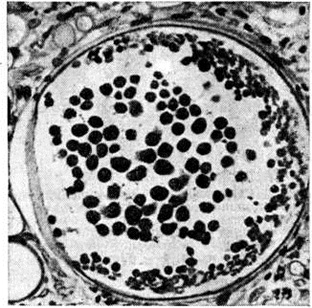

РиноспоридиозРиноспоридиоз (rhinosporidiosis; синонимы: granuloma rhinosporidioticum, morbus Seeber) — редко встречающийся хронический глубокий микоз. Впервые заболевание и возбудителя описал в 1900 год Зибер (G. R. Seeber), ссылаясь при этом на исследование Мальбрана (Malbran, 1892). Риноспоридиоз встречается в странах Юго-Восточной Азии, иногда в Иране, в странах Южной Америки. Случаи заболевания описаны в США, Великобритании, Италии и СССР риноспоридиоз Возбудитель — Rhinosporidium seeberi [синонимы: Coccidiuni seeberi Wernicke (1900), Rhinosporidium kinealyi, Minchin, Fanthum (1905) и другие; относится к классу Phycomycetes, порядку Chytridiales, роду Rhinosporidium. Патогенез неясен. Предполагают, что возбудитель попадает в организм через повреждённые слизистые оболочки. Чаще болеют лица, имеющие контакт с домашними животными (лошади, коровы, мулы), а также работающие на рисовых полях. Возможна гематогенная диссеминация. В поражённых тканях на фоне хронический воспаления, наряду с плазматическими клетками, эозинофилами, лимфоцитами и иногда гигантскими клетками типа Лангханса, видны спорангии — толстостенные округлые образования диаметром до 350 микрометров, наполненные эндоспорами (рисунок), а также отдельные споры (диаметром 7—9 микрометров). Возможны микроабсцессы с некрозами в очагах.